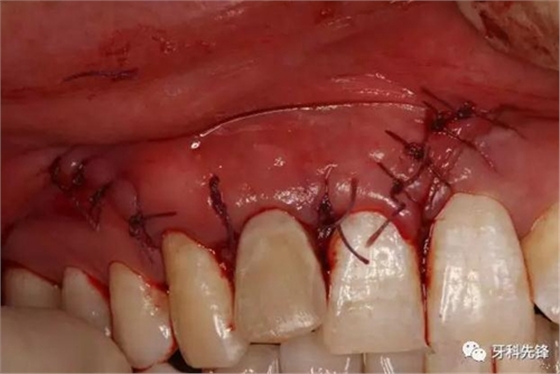

圖18.囊腔填塞膠原蛋白海綿。

圖19縫合。